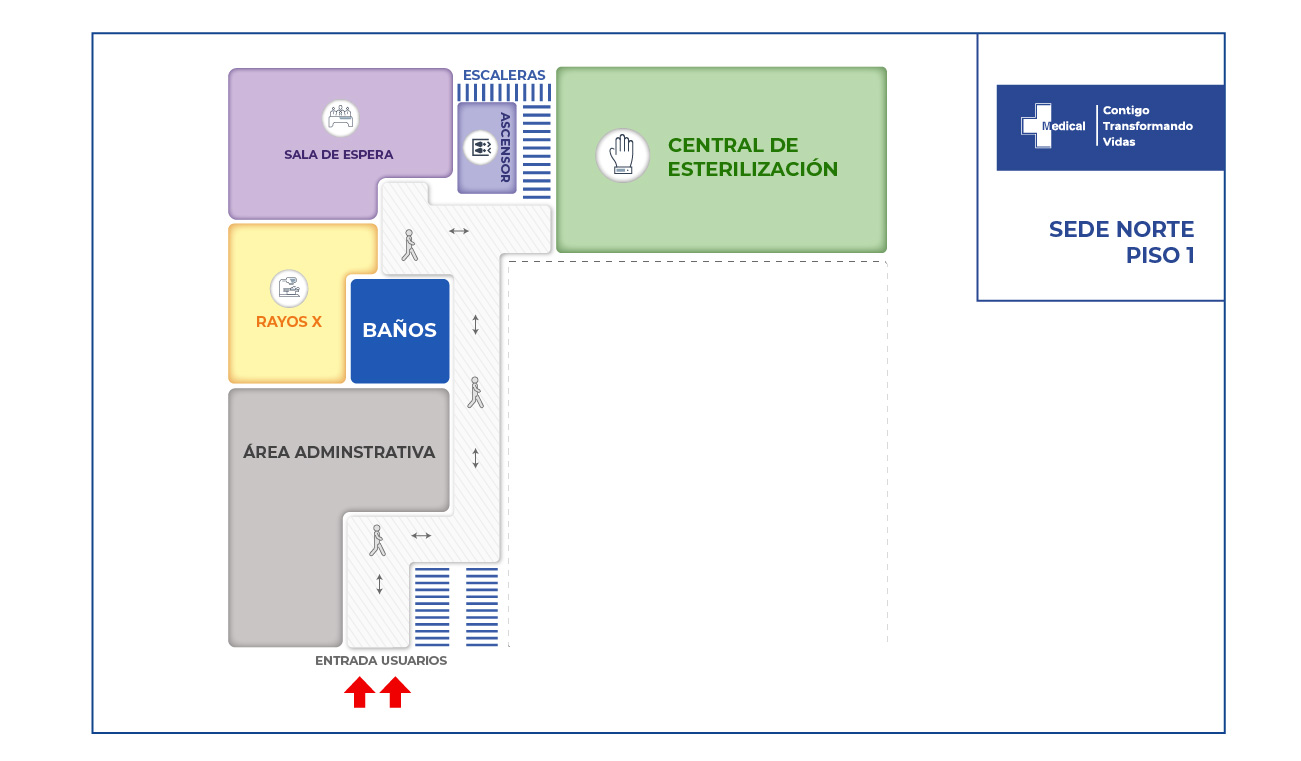

La condición de ingreso es realmente poco alentadora, sin embargo la oportunidad de los servicios, la eficiencia y eficacia que caracteriza a la clínica Medical SAS, ofrece al paciente y su familia todo un equipo interdisciplinario para la atención adecuada y secuencial para este tipo de traumas. Precedida por especialistas en cirugía general, neurocirugía, psicología, psiquiatría, servicios de apoyo terapéutico y radiológico, salas de cirugía, unidad de cuidados intensivos, rehabilitación física, clínica de heridas, entre otros.